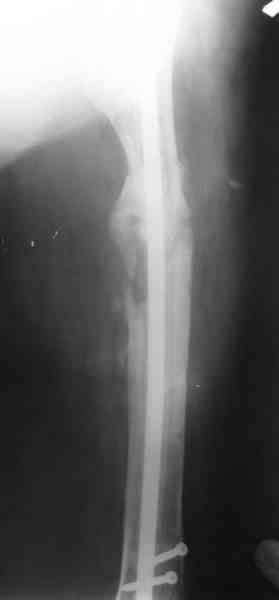

Вчера наш пациент был на контрольном осмотре. Вроде все идет нормально. Рентгенограммы от 25 сентября 2007 г. (прошло 5 месяцев после операции) прилагаю.